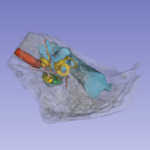

CT-based Atlas of the Head and Neck |

CT-based Atlas of the Ear |